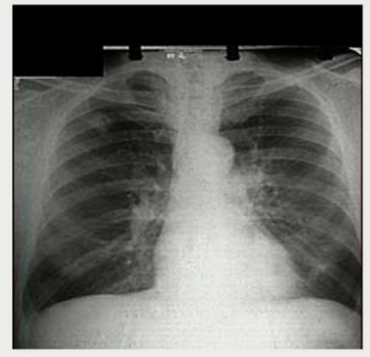

Small Cell Lung Carcinomas can make ADH paraneoplastically

Respiratory disorders such as pneumonia, TB, and asthma